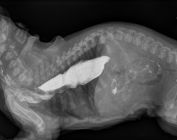

Radio abdominale

Mégaoesophage

Fécalome